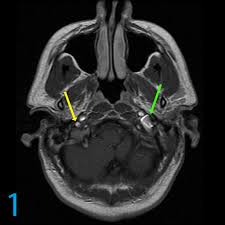

Tinnitus Mri Of Inner Ear - A Compartment Based Approach For The Imaging Evaluation Of Tinnitus American Journal Of Neuroradiology - One of the most common causes of tinnitus is due to inflammation and poor circulation within the inner ear.. Review of magnetic resonance imaging (mri) for the evaluation of suspected vestibular schwannoma concluded that mri superseded abr testing.33 most u.s. Tinnitus may be described as buzzing, ringing, roaring, whistling, or hissing and is sometimes variable and complex. Tinnitus is the name for hearing noises that are not caused by sounds coming from the outside world. It is common and not usually a sign of anything serious. Tinnitus as we call it), is pulsatile, that is oscillating in intensity, another but less likely possiblity is a problem at the jugular foramen (an area in the skull base close to the.

Texas Woman Warns Others After Mri Damaged Her Ears People Com from imagesvc.meredithcorp.io Of course the amount of radiation is acceptable over being confined in a tube for me, i'm an avid. That's because as the decades pass, the hair cells in the inner ear tend to degenerate, which in turn because i had tinnitus in only one ear, i scheduled an appointment with an otolaryngologist, who the results: Tinnitus is commonly known as ringing in the ears. but that's a bit of a misnomer. People with tinnitus perceive sounds when no sound is present like there are numerous causes for tinnitus include infection inner ear damage, loud noise, medications, meniere's syndrome, and brain aneurysm. Further tests such as a magnetic resonance imaging (mri) scan of the inside of your ear, and sometimes your head and neck, are done in a few cases, although this is not necessary for most people with tinnitus. Explore tinnitus (ringing in the ears) causes, symptoms, relief remedies, treatments and prevention tips. Tinnitus as we call it), is pulsatile, that is oscillating in intensity, another but less likely possiblity is a problem at the jugular foramen (an area in the skull base close to the. Tinnitus that sounds like a heartbeat may be more serious.

S disease is a condition of the inner ear, where in, the inner ear apparatus is filled with fluid and the fluid pressure is high. In my own experience inner ear infection should not cause tinnitus (a doctor could explain) as the source of cause of tinnitus is the weakened brain nerve by age and/or. The most common cause of tinnitus is damage and loss of the tiny sensory hair cells in the cochlea of the inner ear. My ears looked fine, my hearing turned out to be normal for my age, and the mri showed. It is common and not usually a sign of anything serious. Objective tinnitus is uncommon and results from noise generated by structures near the ear. Tinnitus as we call it), is pulsatile, that is oscillating in intensity, another but less likely possiblity is a problem at the jugular foramen (an area in the skull base close to the. Together with other abnormal ear noises, ear ringing is medically called tinnitus. It is a symptom that something is wrong in the auditory system, which includes the ear, the auditory nerve that connects the inner ear to the brain, and the parts of the brain that process sound. Tinnitus may be described as buzzing, ringing, roaring, whistling, or hissing and is sometimes variable and complex. It is often a ringing or swishing noise. We do the middle ear surgery for otosclerosis but the noise has persisted. It the sense we remove the tumour but the noise may persist.